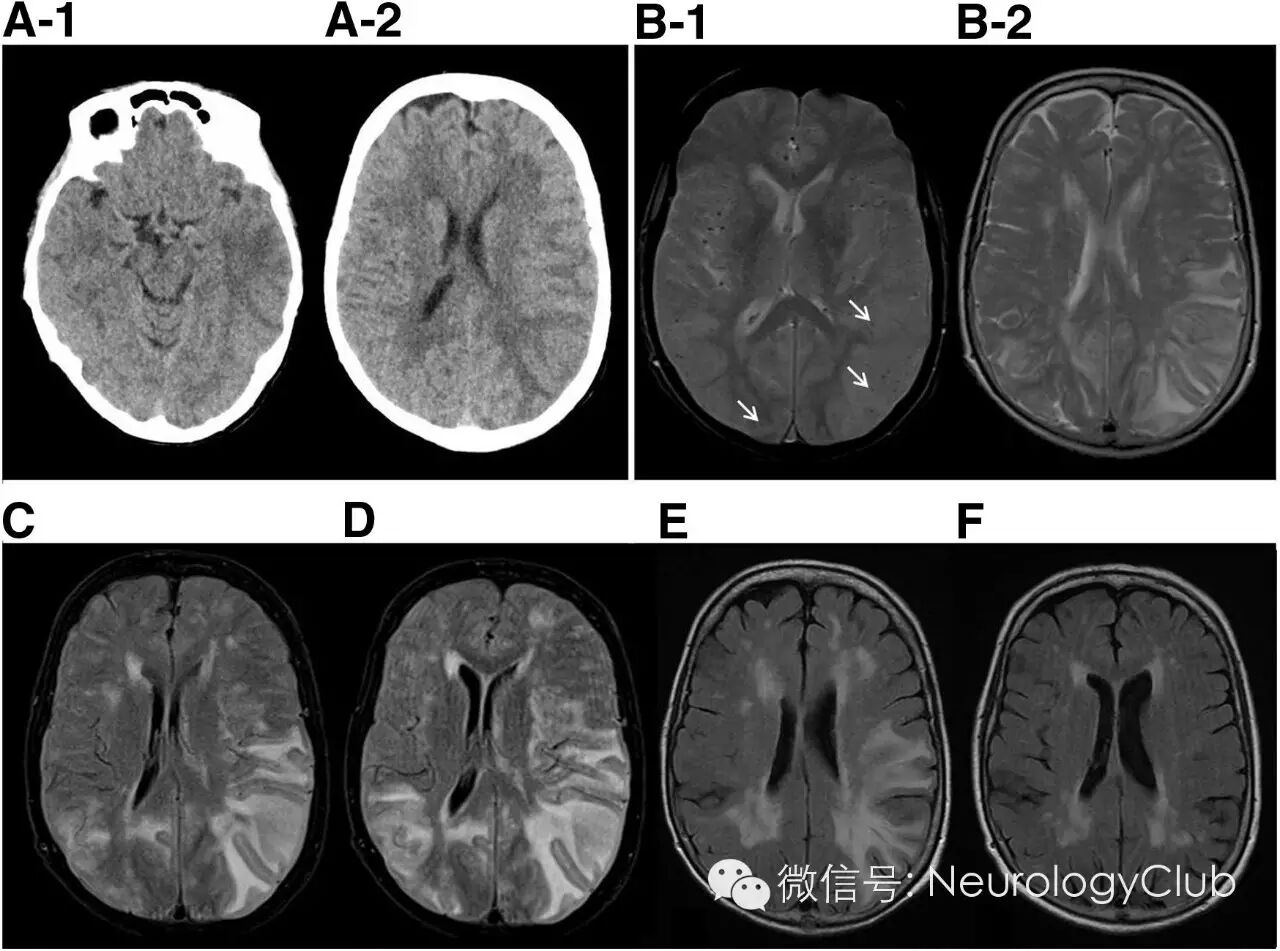

CT平扫可提示皮质下广泛低密度病灶,通常累及颞叶或额叶。几乎所有患者的MRI均异常,主要表现为T2或FLAIR上单发或多发的白质高信号,可伴水肿,病灶常为非对称性,可散在分布或融合成片或呈肿瘤样伴占位效应,灰质较少累及T2*WI上绝大多数患者存在皮质-皮质下微出血,部分患者皮质-皮质下既有微出血又有大出血,只有少数患者表现为大出血。约50%患者有脑白质疏松表现,50%患者有脑膜轻度增强。脑血管造影可见约22%患者存在轻度的双侧脑血管狭窄,主要是大脑中动脉、大脑前动脉的小分支。

(A:CT提示左侧颞叶低密度伴水肿;B-D:入院第2、4、12天的MRI;B-1:T2*WI可见多发微出血[箭头];B-2,C-D:T2WI和FLAIR提示逐渐融合的白质高信号病灶;E-F:激素治疗后复查,30天和9月后的FLAIR上可见T2高信号病灶逐渐减退,仅遗留与年龄相关的白质病变)